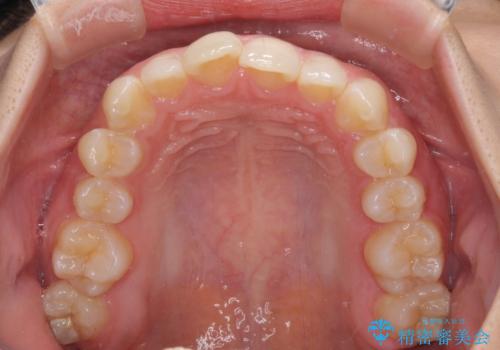

- 前歯のデコボコと歯肉に埋もれている奥歯を気にして来院された患者様です。

インビザラインでの治療を希望されていましたが、左右の下顎大臼歯が歯肉に埋もれており、特に右側は歯軸が顕著に傾斜していたため、インビザライン単独での治療は困難と判断し、ワイヤー装置を併用することとしました。

ワイヤー装置での下顎臼歯改善には時間がかかることが予想されたため、下顎のワイヤー矯正と並行して上顎をインビザラインで整え、その後インビザラインにより上下歯列を整える矯正治療を行うこととしました。

ワイヤー装置を併用したことで、レントゲン写真からも分かるとおり歯軸をしっかりと改善させることができました。